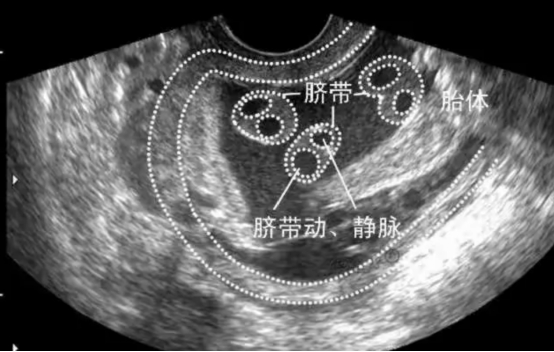

5. 单脐动脉(SUA)

1)是什么?正常的脐带内有2条动脉和1条静脉。单脐动脉则只有1条动脉和1条静脉。

2)意味着什么?大多数只有单脐动脉的宝宝是完全健康的。但它确实略微增加了胎儿伴有心脏、肾脏或其他结构异常,以及染色体异常的风险。

3)怎么办?一旦发现,医生会建议进行一次更详细的胎儿结构筛查(系统B超),特别仔细检查心脏和肾脏。如果排除了其他结构异常,单纯的SUA预后通常良好。